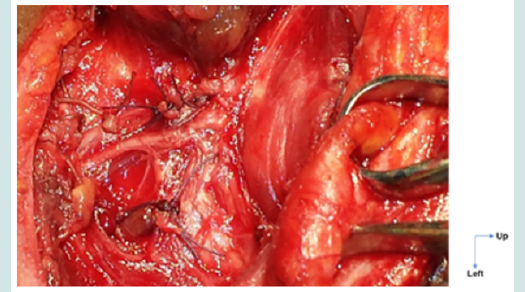

Figure 2: Bifid ILN.